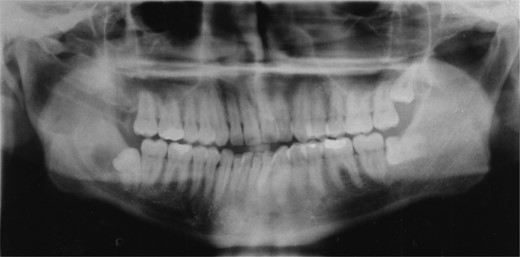

Radiographic examination over the following few months showed new bone formation and within 9 months of the initial biopsy the drain was expelled by formation of new bone (Fig. 3). One year after the commencement of treatment the patient was admitted for enucleation of the cystic remnant. At the time of this procedure a small cyst was removed from the right upper ramus and condylar neck, together, with a separate cyst associated with the lower right wisdom tooth. The patient made an uneventful post-operative recovery and histology revealed two KCOTs with a thick parakeratinized type of epithelium typical of radicular cysts.

Demonstrates bony infill with the nasopharyngeal tube in place.